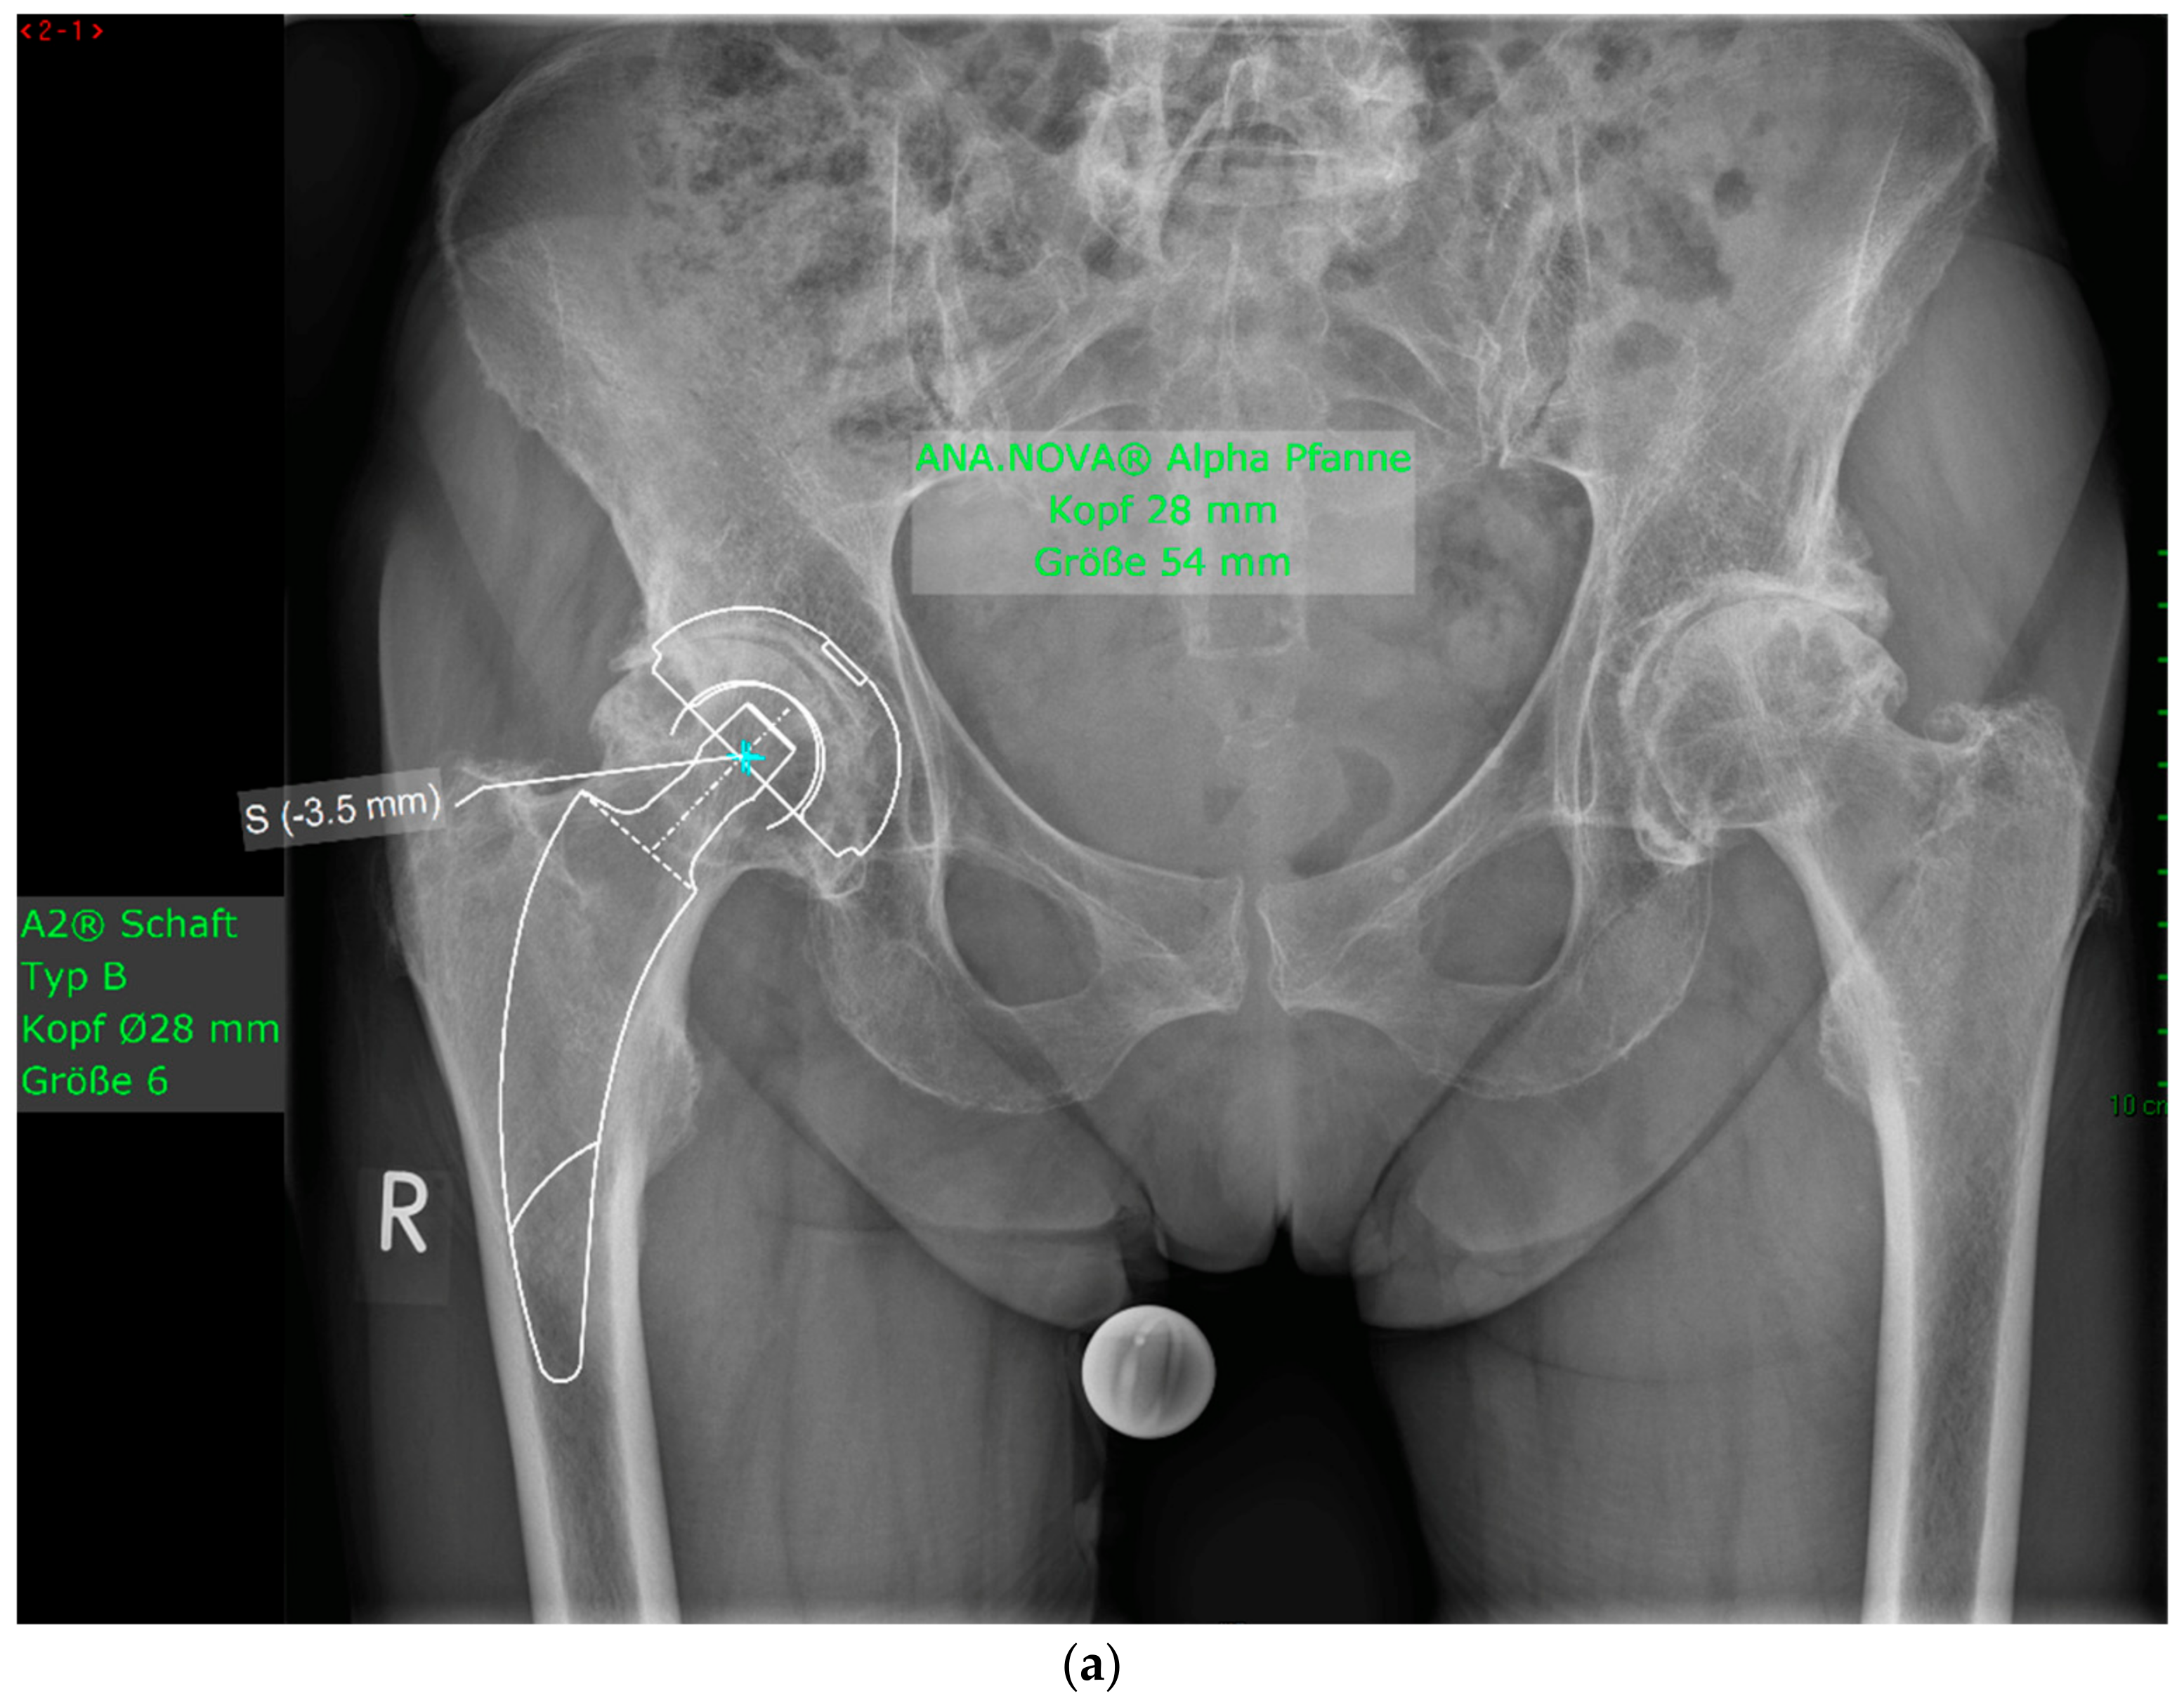

Figure 2.

Case #1: Female patient, 81 years old, with osteoporotic bone, coxa vara, and a Dorr C femur. (a) Preoperative planning for a cemented A2 stem combined with a cementless ANA.NOVA Alpha Cup. The image shows good reconstruction of the leg length and offset. (b,c) Postoperative anteroposterior (b) and axial (c) radiographic imaging 1 week postoperatively. Correct position of the stem and complete cement mantle.

Figure 4.

(a) Case #3: Osteoarthritis, female, 81 years old, preoperative planning. (b) Correct implant position 1 week postoperatively. Homogeneous cement mantle.